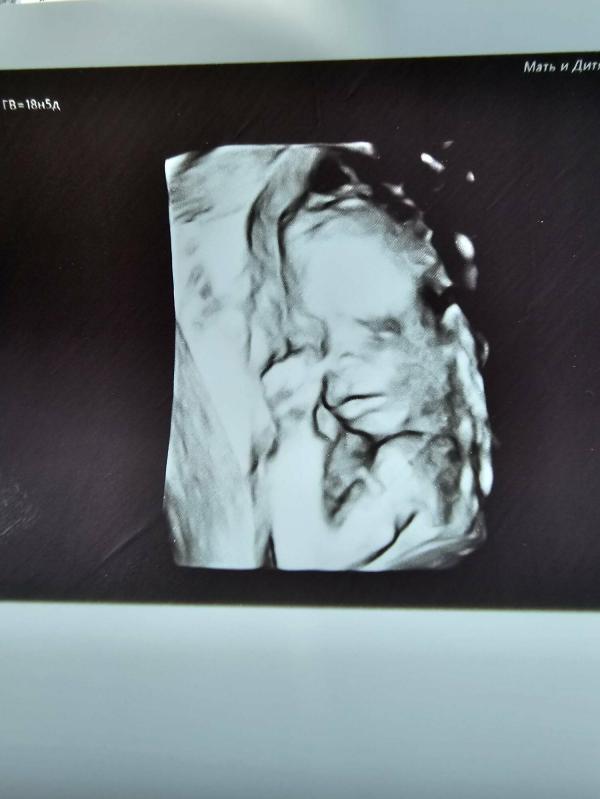

Сегодня была на узи, нам 18,5 неделек. Все соответствует сроку 🙏 Сегодня я ощутила, как она может пинаться во всю силу 😄Это было больно. Не успев поднести датчик, малышка начала пинаться. А потом уже и датчик пинать, не понравилось 😄 Почти все Время узи 20 минут, она пиналась и пиналась больно 😄. Весит 254 гр 🥰❤️

Единственное что теперь беспокоит, это низкая плацента, 10мм от вн.зева (( Надеюсь поднимется. Скоро ещё на скрининг, посмотрим, что там напишут.